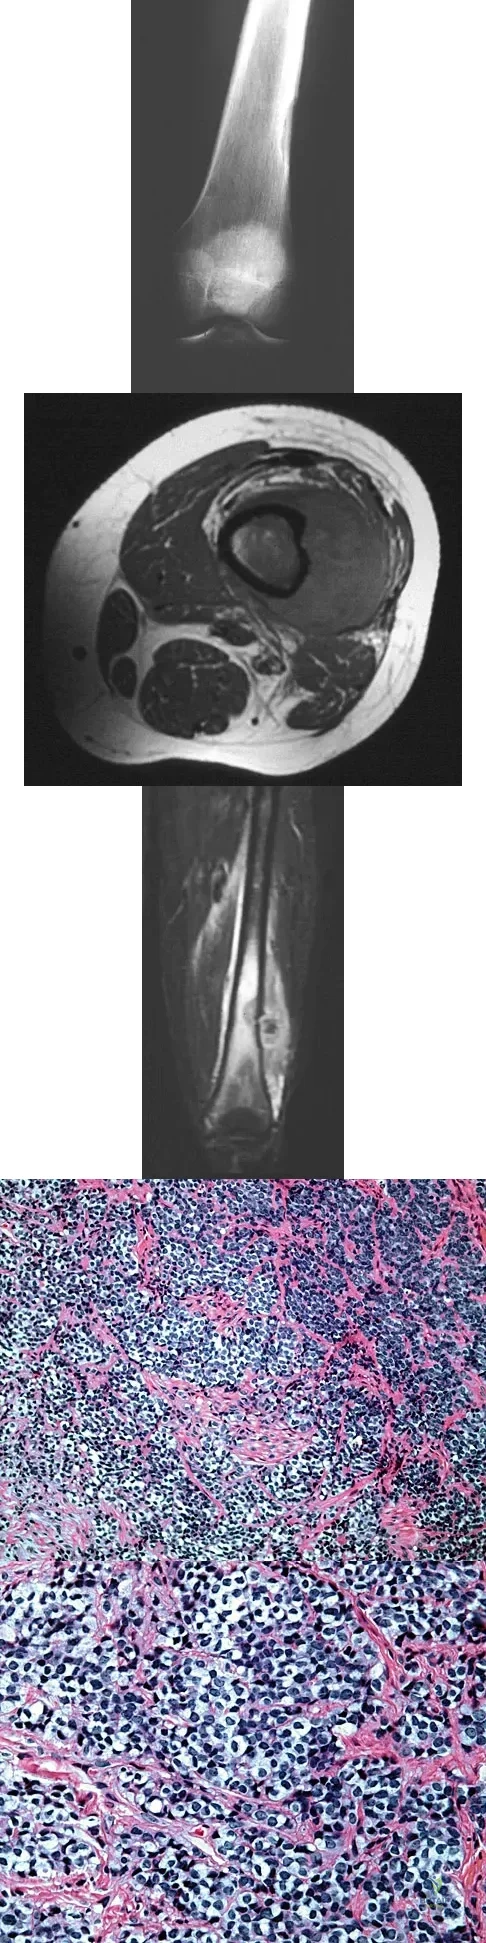

Question 8

A 45-year-old man has had left thigh pain for the past 4 months. An AP radiograph, bone scan, MRI scans, and biopsy specimens are shown in Figures 6a through 6f. What is the most appropriate treatment?

A 13-year-old boy has a painless "knot" over his left hip. History reveals that he injured his left hip playing soccer 4 months ago. A radiograph and MRI scan obtained at the time of injury are shown in Figures 7a and 7b. He is very active and is currently asymptomatic. A current radiograph is shown in Figure 7c. What is the next most appropriate step in management?

Explanation